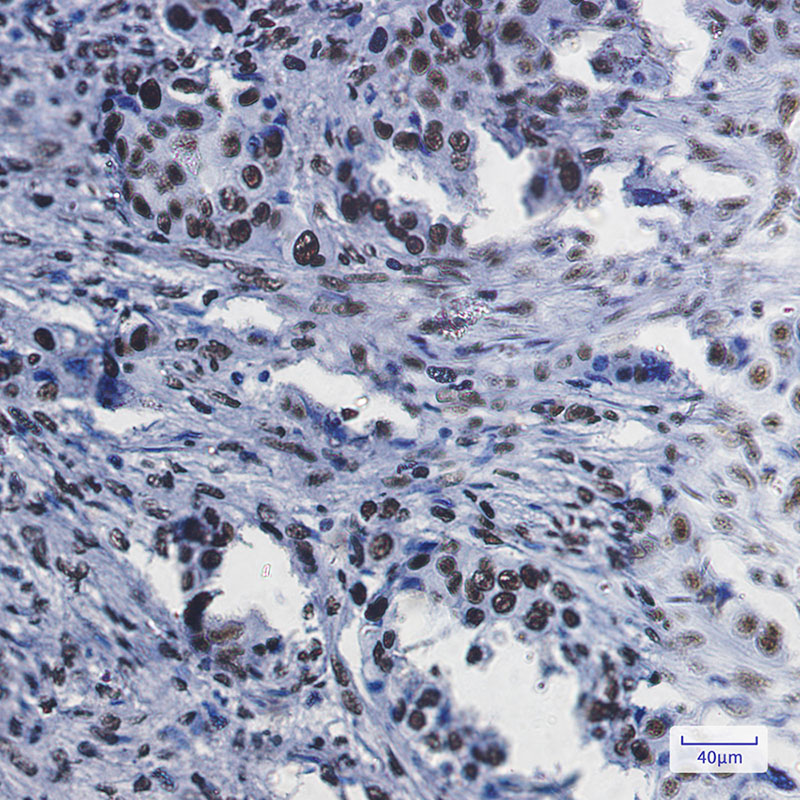

Immunohistochemistry analysis of paraffin-embedded Human lung cancer using RbAp48 antibody.High-pressure and temperature Sodium Citrate pH 6.0 was used for antigen retrieval.